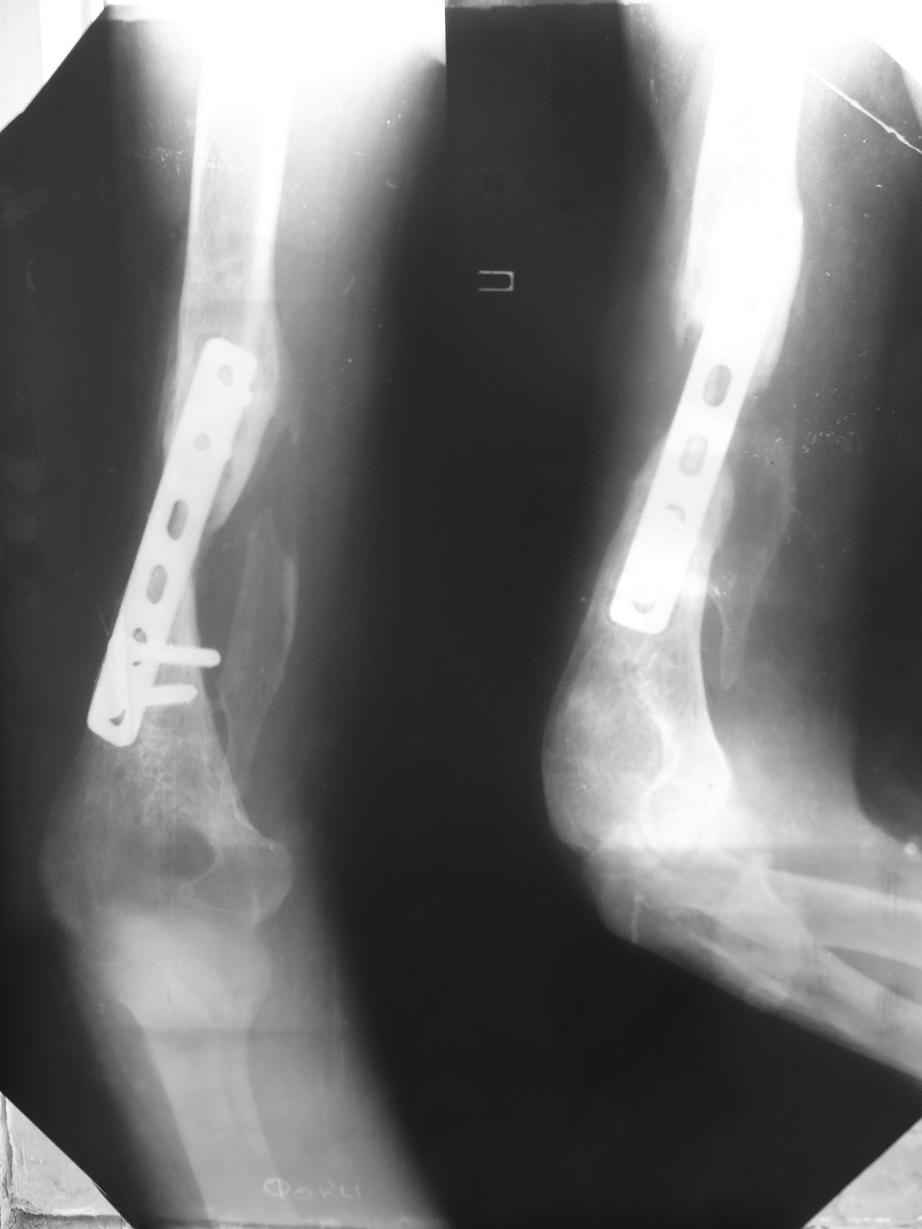

Первичную пластину убрали недели 6 назад из переднего оригинального доступа, и из-за подозрительности тканей вокруг пластины, решили провести реконструкцию поэтапно.

После промывки и дебридмента для уверенности уложили антибиотический цемент. Культура из раны в последующем была отрицательная.

Хотя сам не стороннник применения более массивных

имплантов для плеча, но для этого случая сделали

исключение. На снимке 4А диаметр мягких ткани около 20 см, при весе больной более 135 кг, и также выступление Андрея Волны подстегнуло к применению более массивной 4.5 мм локинг пластины.